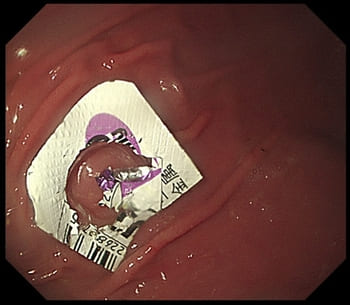

以下は、2,6kgのチワワが誤飲したPTP包装の内視鏡画像です。

2.6kgチワワが誤飲した胃の中のPTP包装の内視鏡画像

2.6kgチワワが誤飲した胃の中のPTP包装

内視鏡画像にて

PTP包装はレントゲンではうつらないので、麻酔した上で内視鏡検査しなくてはいけません。